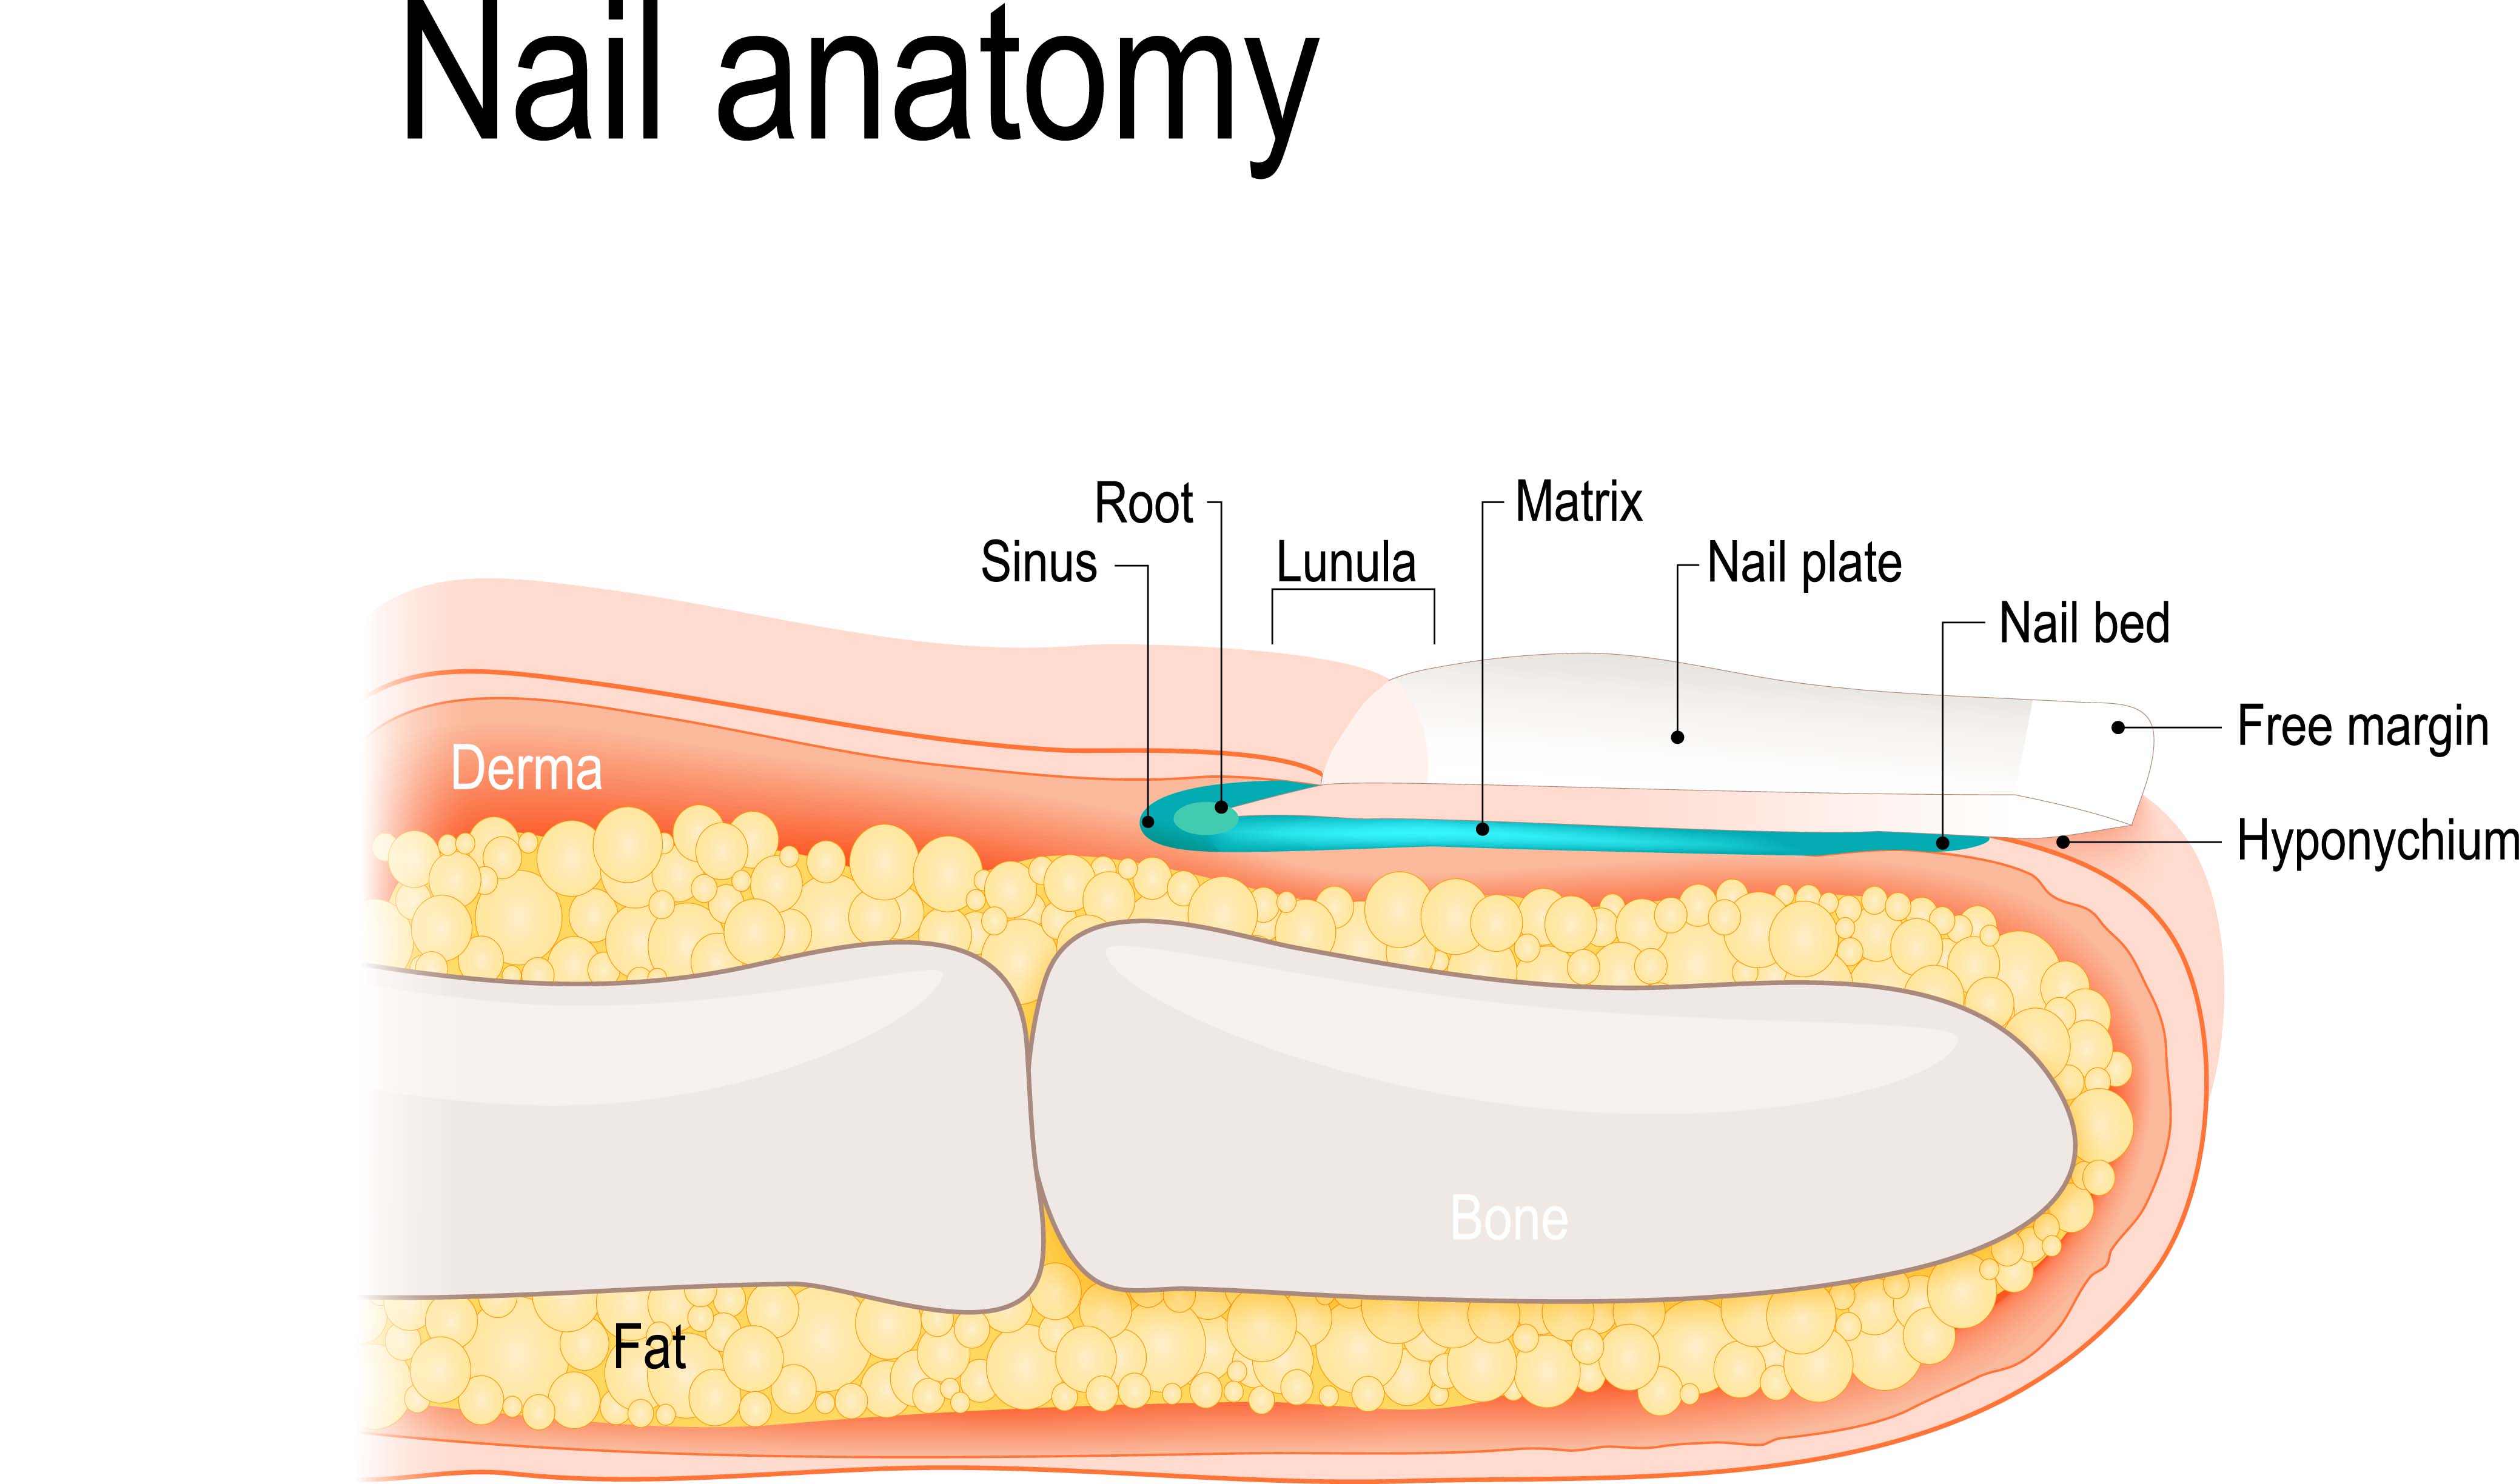

Toenail Anatomy Diagram

Toenail Anatomy Diagram